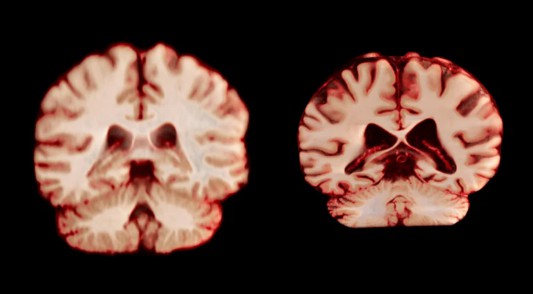

健康大脑(左)和患有阿尔茨海默病的大脑。图片来源:Anatomical Travelogue/SPL

临床上被诊断为阿尔茨海默病的女性人数几乎是男性的两倍,而衰老是该疾病的最大风险因素。这一现象促使研究者探索大脑衰老过程中与性别相关的差异。“如果女性大脑衰退程度更严重,或许能解释她们的阿尔茨海默病患病率更高。”论文第一兼通讯作者、挪威奥斯陆大学的Anne Ravndal表示。

结果显示,总体而言,男性大脑多个区域的体积缩减幅度大于女性。例如,负责处理触觉、疼痛、温度感知及身体位置和运动感知的中央后回,男性每年缩减2.0%,而女性每年仅缩减1.2%。

澳大利亚莫纳什大学的Amy Brodtmann指出:“如果这些大脑变化与阿尔茨海默病的发病有关,那么研究理应发现女性在与该疾病相关的脑区,如参与记忆功能的海马体和楔前叶出现更大的衰退。但实际并非如此。”